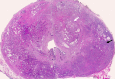

Materials and methods: In this institutional review board-approved (with waiver of informed consent), HIPAA-compliant study, 38 foci of carcinoma, 38 SH nodules, and 38 GH nodules in the CG were analyzed in 49 patients (26 with CG carcinoma) who underwent preoperative endorectal magnetic resonance (MR) imaging and radical prostatectomy. All carcinomas and hyperplastic foci on MR images were localized on the basis of histopathologic correlation. The apparent diffusion coefficient (ADC), the contrast agent transfer rate between blood and tissue (K(trans)), and extravascular extracellular fractional volume values for all carcinoma, SH, and GH foci were calculated. The mean, standard deviation, 95% confidence interval (CI), and range of each parameter were calculated. Receiver operating characteristic (ROC) and multivariate logistic regression analyses were performed for differentiation of CG cancer from SH and GH foci.

Results: The average ADCs (× 10(-3) mm(2)/sec) were 1.05 (95% CI: 0.97, 1.11), 1.27 (95% CI: 1.20, 1.33), and 1.73 (95% CI: 1.64, 1.83), respectively, in CG carcinoma, SH foci, and GH foci and differed significantly, yielding areas under the ROC curve (AUCs) of 0.99 and 0.78, respectively, for differentiation of carcinoma from GH and SH. Perfusion parameters were similar in CG carcinomas and SH foci, with K(trans) yielding the greatest AUCs (0.75 and 0.58, respectively). Adding K(trans) to ADC in ROC analysis to differentiate CG carcinoma from SH increased sensitivity from 38% to 57% at 90% specificity without noticeably increasing the AUC (0.79).

Conclusion: ADCs differ significantly between CG carcinoma, SH, and GH, and the use of them can improve the differentiation of CG cancer from SH and GH. Combining K(trans) with ADC can potentially improve the detection of CG cancer.